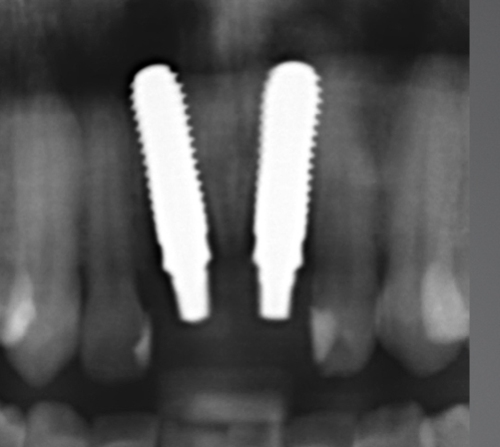

IMPLANTATE AUS KERAMIK

Vorteile: natürliche Ästhetik, Biokompatibilität, Langlebigkeit, Stabilität, Zahnfleischfreundlichkeit und Knochenfreundlichkeit.

Seit mehr als 15 Jahren verwenden wir in der Tagesklinik ausschließlich Implantate aus Keramik.

- Natürliche Ästhetik: Implantate aus Keramik sehen aus wie natürliche Zähne und harmonieren perfekt mit dem restlichen Gebiss. Sie bieten eine ästhetisch ansprechende Lösung für den Zahnersatz.

- Biokompatibilität und Allergiefreiheit: Keramikimplantate sind biokompatibel, was bedeutet, dass sie gut vom Körper vertragen werden. Im Gegensatz zu Metallimplantaten verursachen sie keine allergischen Reaktionen oder Unverträglichkeiten.

- Langlebigkeit und Stabilität: Implantate sind äußerst haltbar und können bei guter Pflege ein Leben lang halten. Sie bieten eine stabile Grundlage für Zahnprothesen, Kronen oder Brücken und gewährleisten so eine zuverlässige Funktion.

- Zahnfleischfreundlichkeit: Implantate aus Keramik zeichnen sich durch ihre zahnfleischfreundlichen Eigenschaften aus. Sie verursachen keine Reizungen oder Entzündungen des Zahnfleischs und fördern so eine optimale Mundgesundheit.

- Knochenfreundlichkeit: Implantate aus Keramik unterstützen den Knochenabbau nicht. Im Gegenteil, sie fördern die Knochenintegration und stimulieren das Knochenwachstum, was langfristig die Stabilität des Kieferknochens gewährleistet